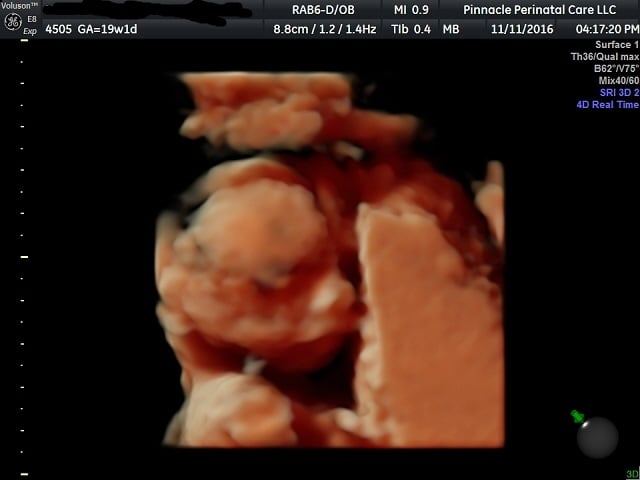

Anatomy scan at 19 weeks, 1 day. It's another obvious little boy! Placenta is posterior (good news having had a previous section), baby looks good. He was very cooperative. 3D was an unexpected little treat!